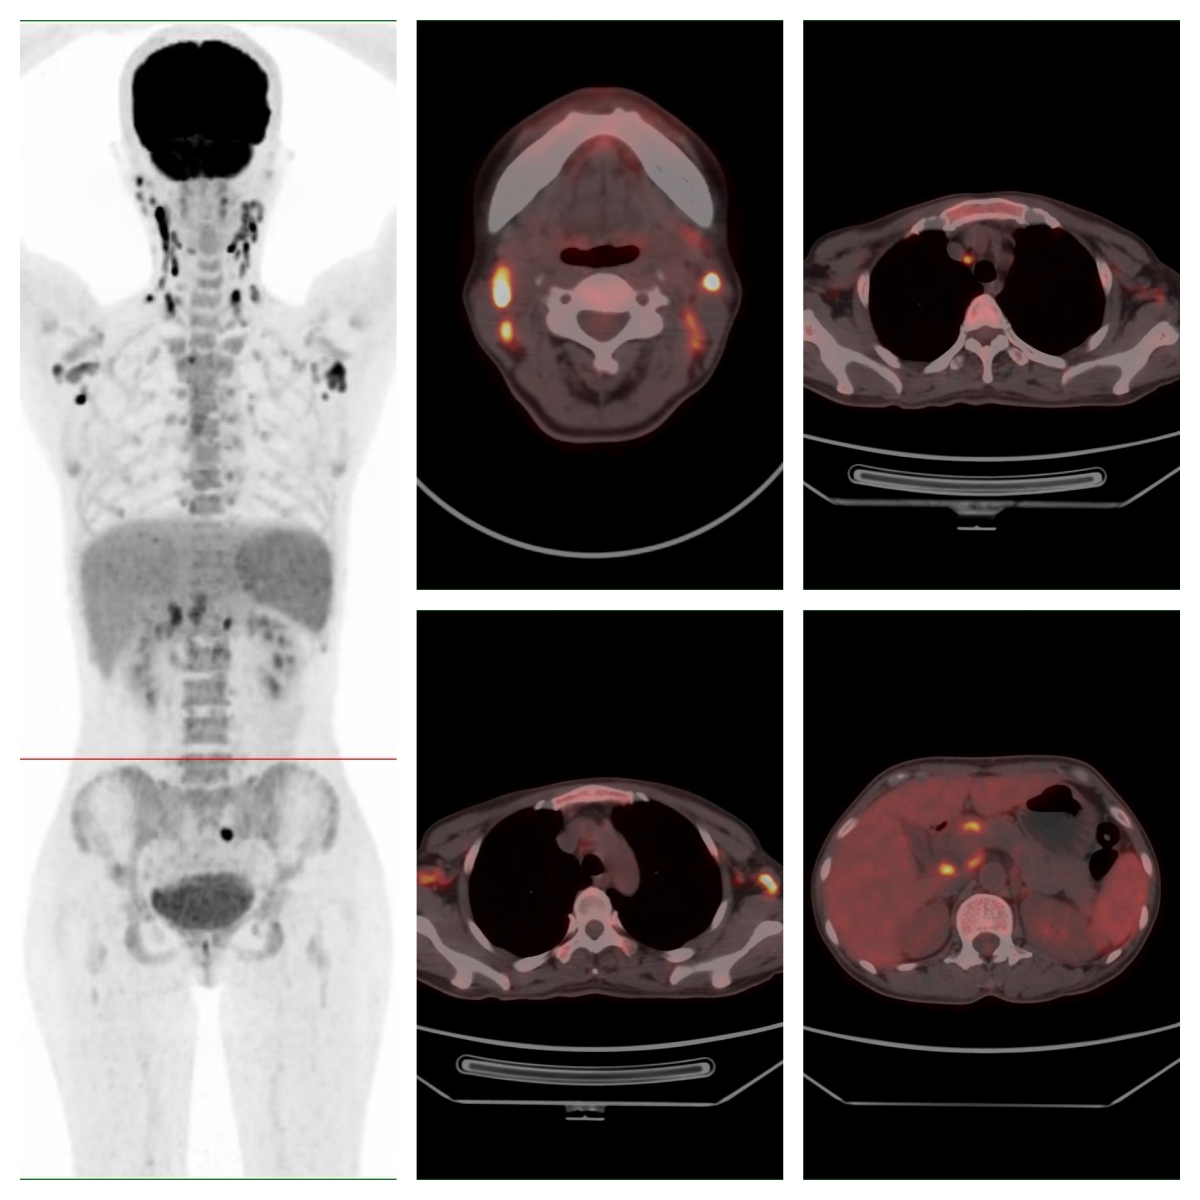

為明確病情,完善PET/CT檢查

PET/CT示全身多處淋巴結、多處骨骼及脾臟代謝異常,考慮系統性疾病(圖示);顯像劑攝取最高者位于右側頸部Ⅱ區,SUVmax約19.6。

圖 全身多處淋巴結、骨骼及脾臟代謝異常。

經多學科會診,對右側頸部代謝最高的淋巴結進行了完整切除活檢,病理示外周T細胞淋巴瘤-非特指型。